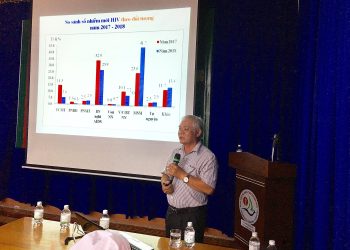

Lớp truyền thông phòng chống HIV/ AIDS

TỔ CHỨC LỚP TRUYỀN THÔNG PHÒNG, CHỐNG HIV/AIDS CHO CÁN BỘ CÔNG NHÂN VIÊN BỆNH VIỆN NĂM 2019 Nhằm thực...